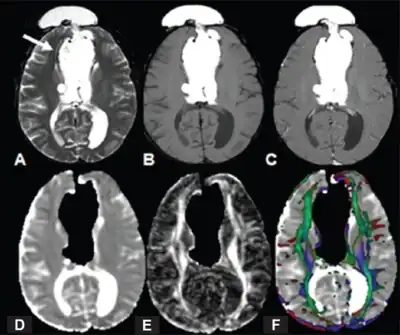

| MRI images of three patients in the sagittal plane. A and B: Complete agenesis of the corpus callosum. C: Complete agenesis of both the corpus callosum and the anterior commissure. | |